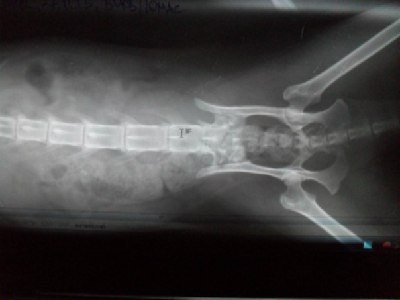

Вет.врач, к которому мы обратились сказал, что впервые видит такое: У кошки переломов нет, но у нее аномалия позвоночника, отсутствует один из крестцовых позвонков. В следствие механического воздействия(удар или падение) произошла декомпрессия нервных структур в области крестца, соответственно у кошки отказали ноги и произошло нарушение мочеиспускания и дефекации.

еще снимки

Аномалии в крестцовом отделе я не вижу. У нее присутствуют все 3 крестцовые позвонки.

Сделайте еще рентген всего позвоночника...И можно сделать МРТ, это даст точный диагноз где проблема и насколько она серьезная...По Вашему снимку, возможно, есть проблема в крестце...Но качество снимка не позволяет точно сказать...Переделайте его...

Если снимок будет будет с таким же качеством,как и предыдущие, то нет смысла выкладывать. Если рентген цифровой, лучше прислать ссылку на фаил с первоначальным снимком. А не перефотографировать и выкладывать сюда.